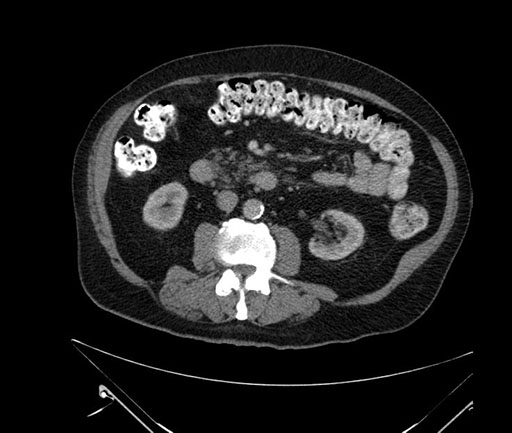

Imaging Analysis

Look through the patient's CT scan to identify any areas of concern for the necessary procedure.

Based on your CT findings, which issue(s) would give reason for "planned slowing down moment(s)" in this case?

Considering a standard Whipple procedure, what step(s) of the operation would you do differently in this case?